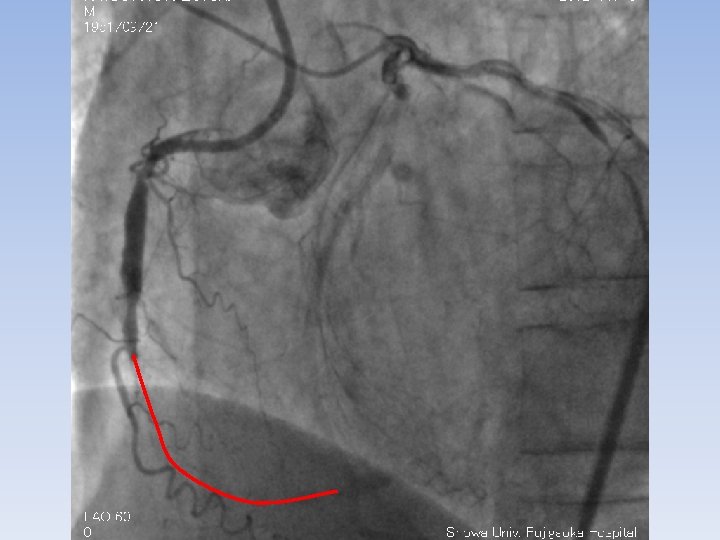

RCA #2 long CTO LAD #6 90% LCX #13 90%

XT-R Gaia-First Gaia-Second with Corsair